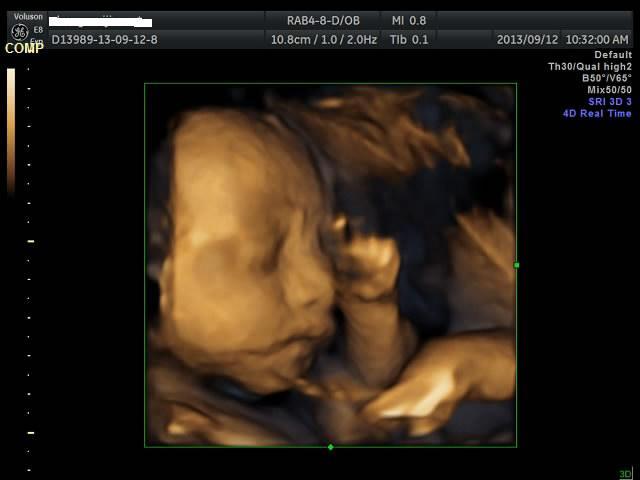

有没有能够帮我看看是千金还是帅哥的朋友?只是好奇是应该准备蓝色衣服还是应该买粉色衣服呢? 点击展开 匿名用户 2013-09-12 20:44 为您推荐: 其他回答 吓死我了... 匿名用户 2013-09-12 20:57 看不出来啊,买米黄色的吧 不论男女,都很好看 匿名用户 2013-09-12 20:57 帅哥的朋友吧,最好选粉红色的 匿名用户 2013-09-12 20:53 要怎么看才好 匿名用户 2013-09-12 20:48 千金,买粉红的 匿名用户 2013-09-12 20:47 相关问题 谁帮我看看是千金还是帅哥! 来看看我家24天的小帅哥,穿粉色衣服么么哒 张凡帅吗?很好奇听说是个帅哥,求解!!!!!!!